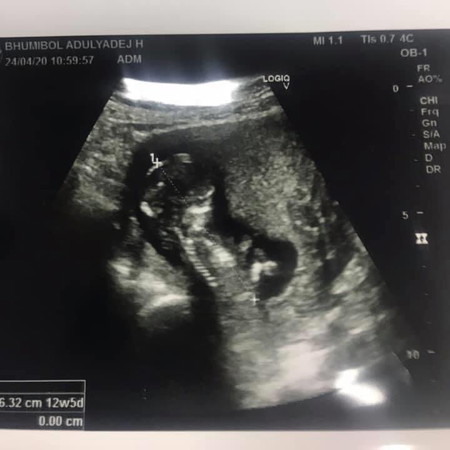

ไม่เห็นเพศค่ะ เห็นแต่ขา เป็นรูปด้านข้าง น้องยังเล็กเกินไปด้วยแค่ 12 สัปดาห์เอง

ยังไม่เห็นนะคะ ช่วง 16 สัปดาห์นี่ชัดเจนเลยค่ะ ถ้าน้องยอมอ้าขาให้ดูนะคะ

ของเราซาวตอน11สัปดาห์5วันหมอบอกว่าญ #ทีมพฤศจิกายน

ตามทฤษฎีฝรั่งศีรษะทรงนี้น่าจะผญค่ะ